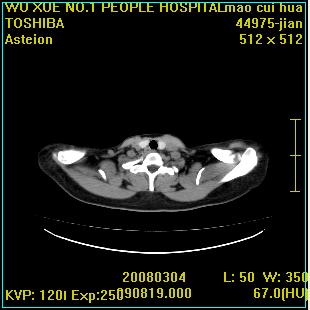

标题: CT12025:男,50岁,左肩活动受限半年。 [打印本页]

标题: CT12025:男,50岁,左肩活动受限半年。

左侧肱骨头密度不均匀,高低混杂,周围软组织略肿胀,考虑结核性病变。

考虑左侧肱骨慢性骨髓炎。

左侧肱骨头密度不均匀,高低混杂,髓腔密度稍高,周围软组织略肿胀,肌间隙模糊,考虑慢性骨髓炎可能。密切结合临床!